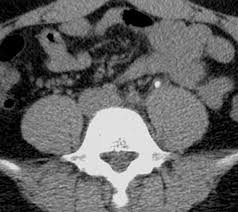

21. Your patient is a 45 year old male that presents with flank pain, nausea and vomiting. His CT scan is below. What is his diagnosis?

A. Phlebolith

B. Ureter Stone

C. Amyloidosis

D. CREST Syndrome